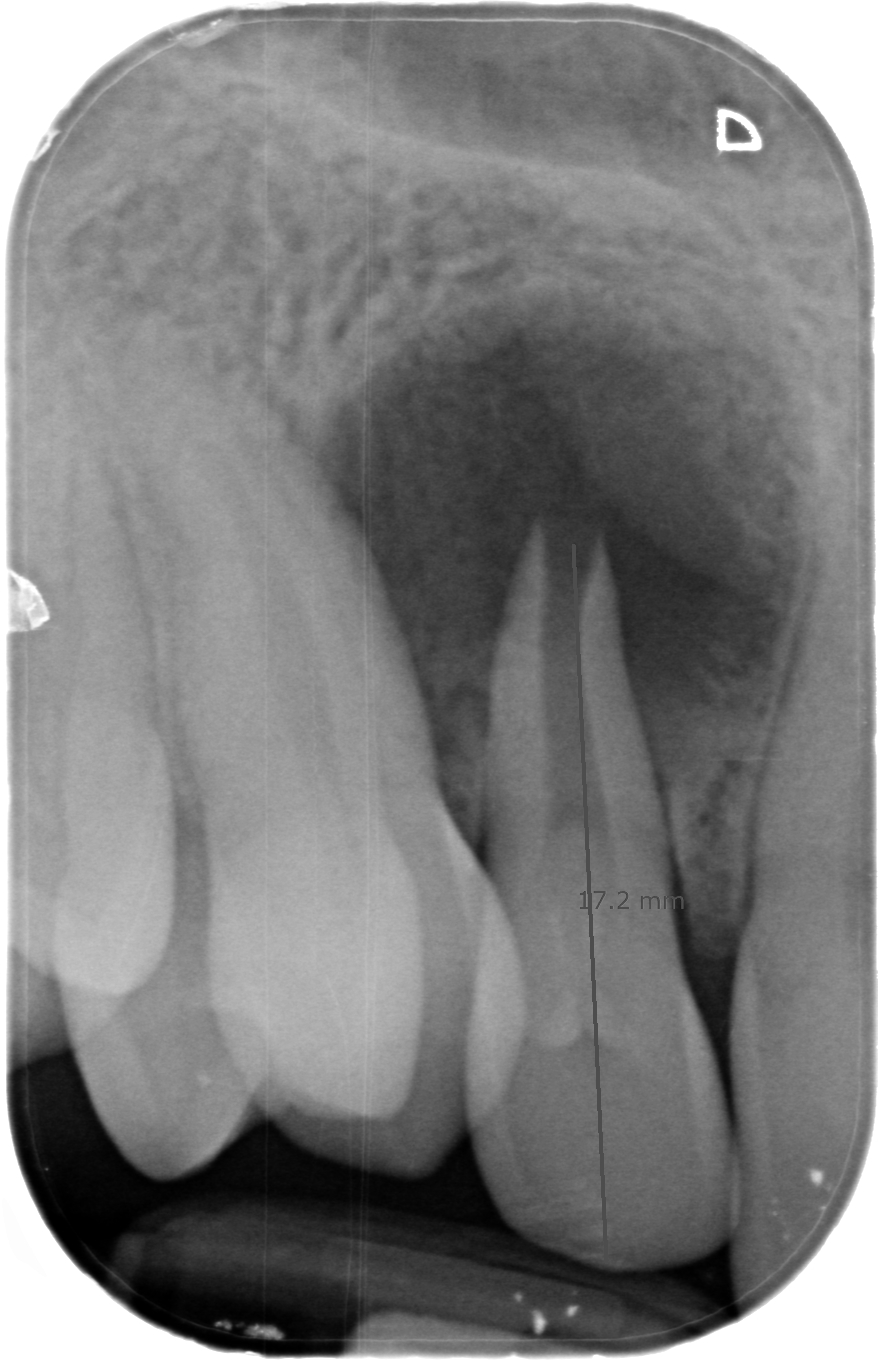

Implantes e implantoprótesis en Segovia

Es la especialidad dedicada a reponer los dientes perdidos/ausentes mediante la colocación de un implante, un “tornillo” de titanio anclado al hueso, y que una vez se ha osteointegrado (soldado al hueso), permite colocar una corona protésica atornillada directamente al implante.

En Clidentse contamos con el Dr. Ángel Silmi para esta especialidad, que es sin duda la opción ideal y más conservadora para reponer los dientes perdidos y/o ausentes. De otra forma, la prótesis fija convencional sobre

diente exige tallar (desgastar) los dientes adyacentes a la ausencia, los cuales hacen de pilares de un puente de 3 piezas para reponer el diente perdido. Con los implantes dentales, esta antigua opción terapéutica fija está desaconsejada. Hoy día se tiende a hacer una Odontología Mínimamente Invasiva. Y tallar los dientes supone un tratamiento excesivamente traumático y debilitante. La resistencia de los dientes está relacionada directamente con la cantidad de diente sano remanente.